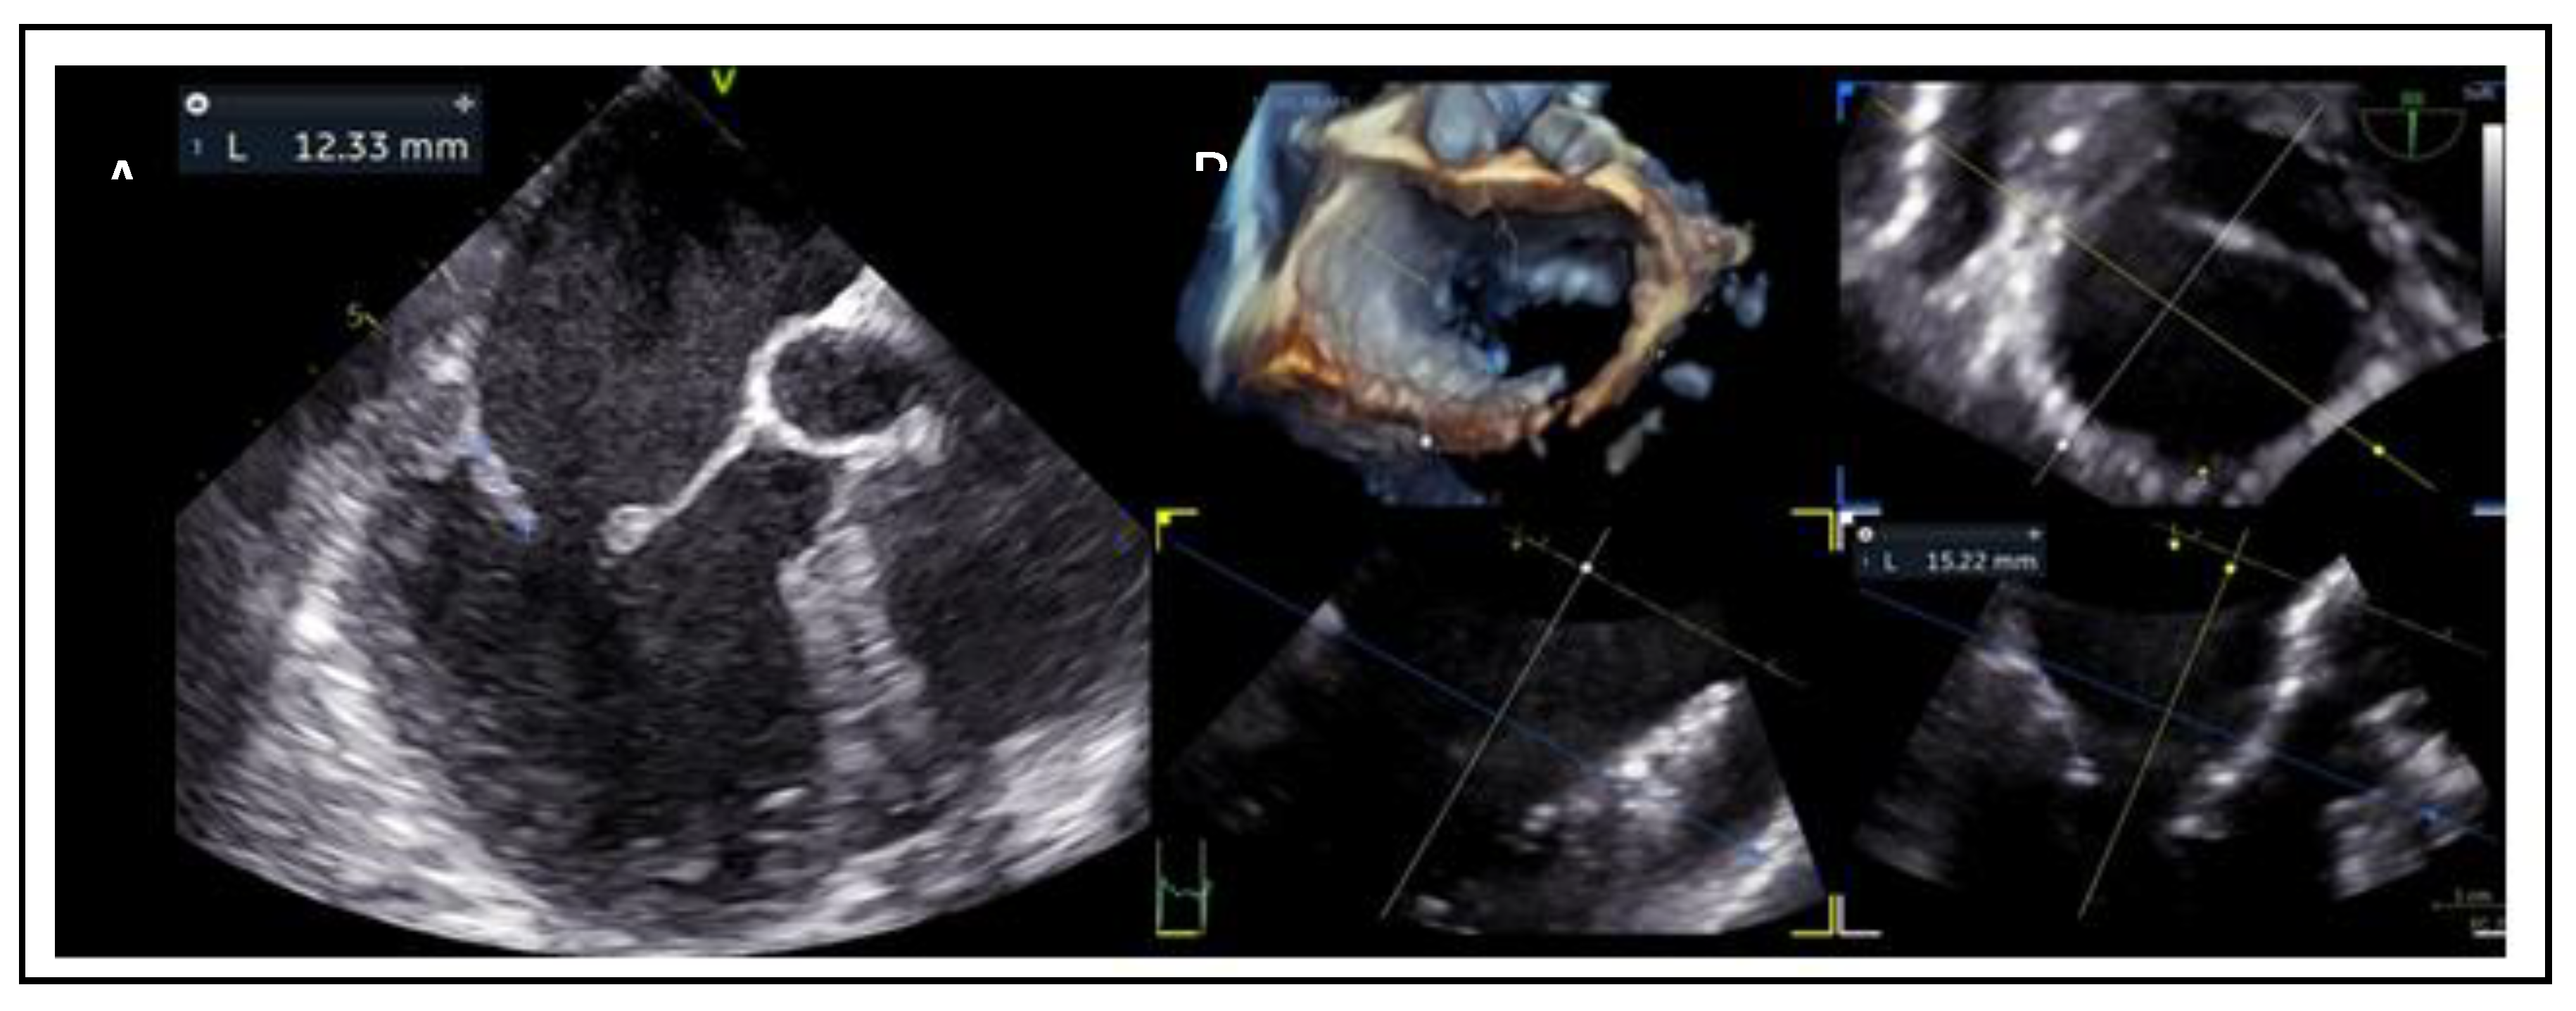

5. Anatomical Considerations for TEER

- Mitral annulus dimensions: Small dimensions of annulus (annulus area, anterior-posterior and medial-lateral diameters) should also be considered in the screening process.

7.1. Mitral Valve Anatomy

7.2. Posterior Leaflet Length